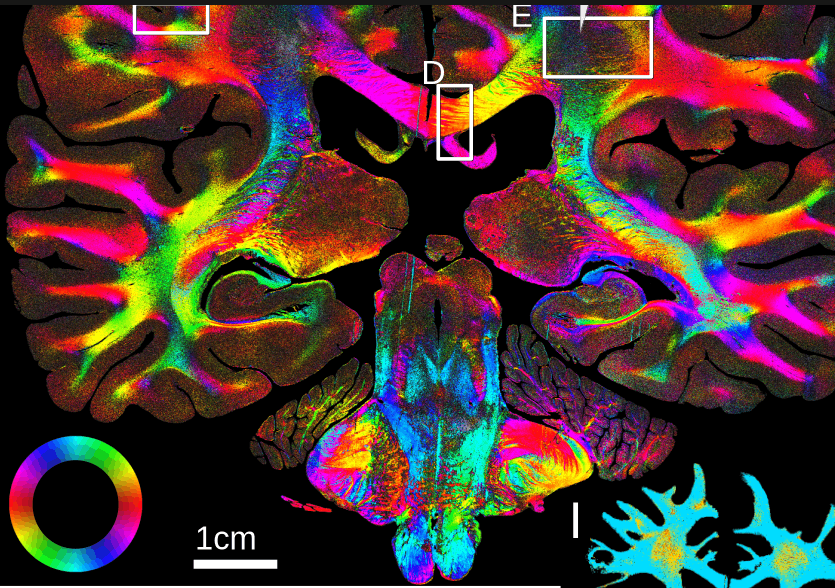

The result is a color-coded map of all the fiber orientations. Each color represents a different angle, providing a detailed view of the fiber bundles connecting the different brain regions. In neurodegenerative diseases like Parkinson’s, the orientation of these fibers provides clues about disease progression and which areas are involved.

A scan of a brain section with the colored fibers. © Georgiadis et al., Nature Communications 16:9572, 2025